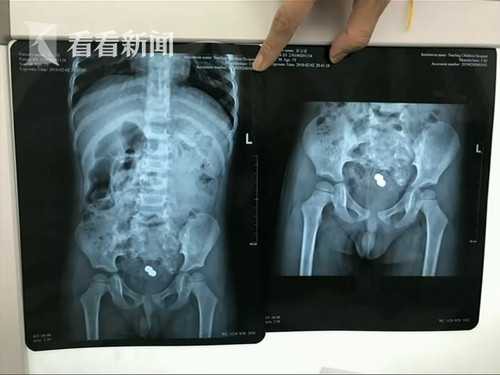

Hình ảnh chụp x-quang được bác sĩ cung cấp.

Dị vật mà bé Khang Khang nuốt phải là một món đồ chơi có góc cạnh.

Sau khi sử dụng biện pháp nội soi cùng 1 số dụng cụ chuyên nghiệp, bác sĩ đã gắp được 1 chú chó đồ chơi dài 2cm, rộng 1.5cm ra khỏi cơ thể bé trai. Bác sĩ nói thêm, nếu cứu chữa chậm trễ, ruột non của bé có thể bị hỏng vĩnh viễn.